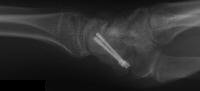

The nonunion was reconstructed by removing the hardware, iliac bone graft and two Herbert screws placed through new paths. Cancellous bone was packed into the old screw hole.